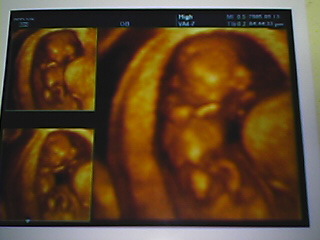

昨日の検診の時に、今3D検査をやる時期だと言われた。

実は、診断書とかの関係で、産科に来たので、念のために3D検査ができないか聞いてみた。

そしたら、ちょうどあいているということで・・・。

3D検査すごいねーーー。

顔がみえるよーーー。

なんか、あるみちゃんにとっても近くなった気分です。

うれしいなーー。